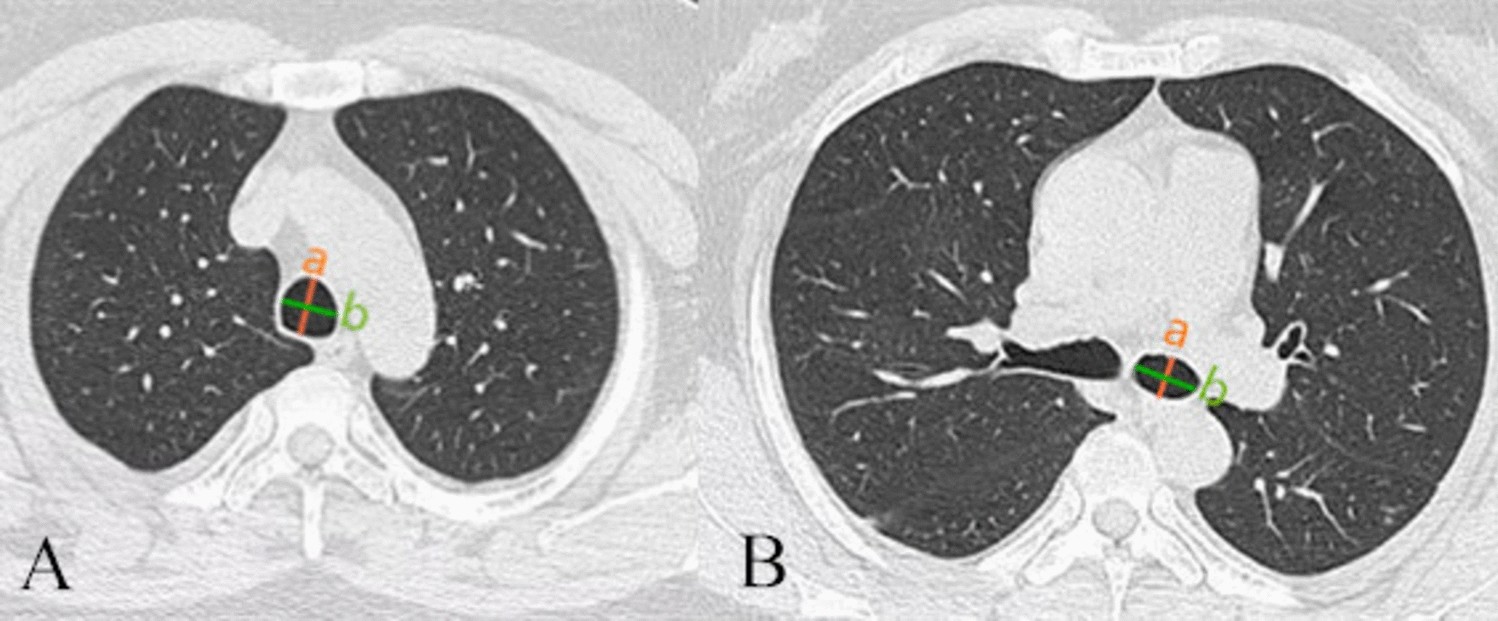

Figure 2

(A) a: Longitudinal inner diameter of trachea, (b) Transverse inner diameter of trachea; (B) (a) Longitudinal inner diameter of bronchus, (b) Transverse inner diameter of bronchus.